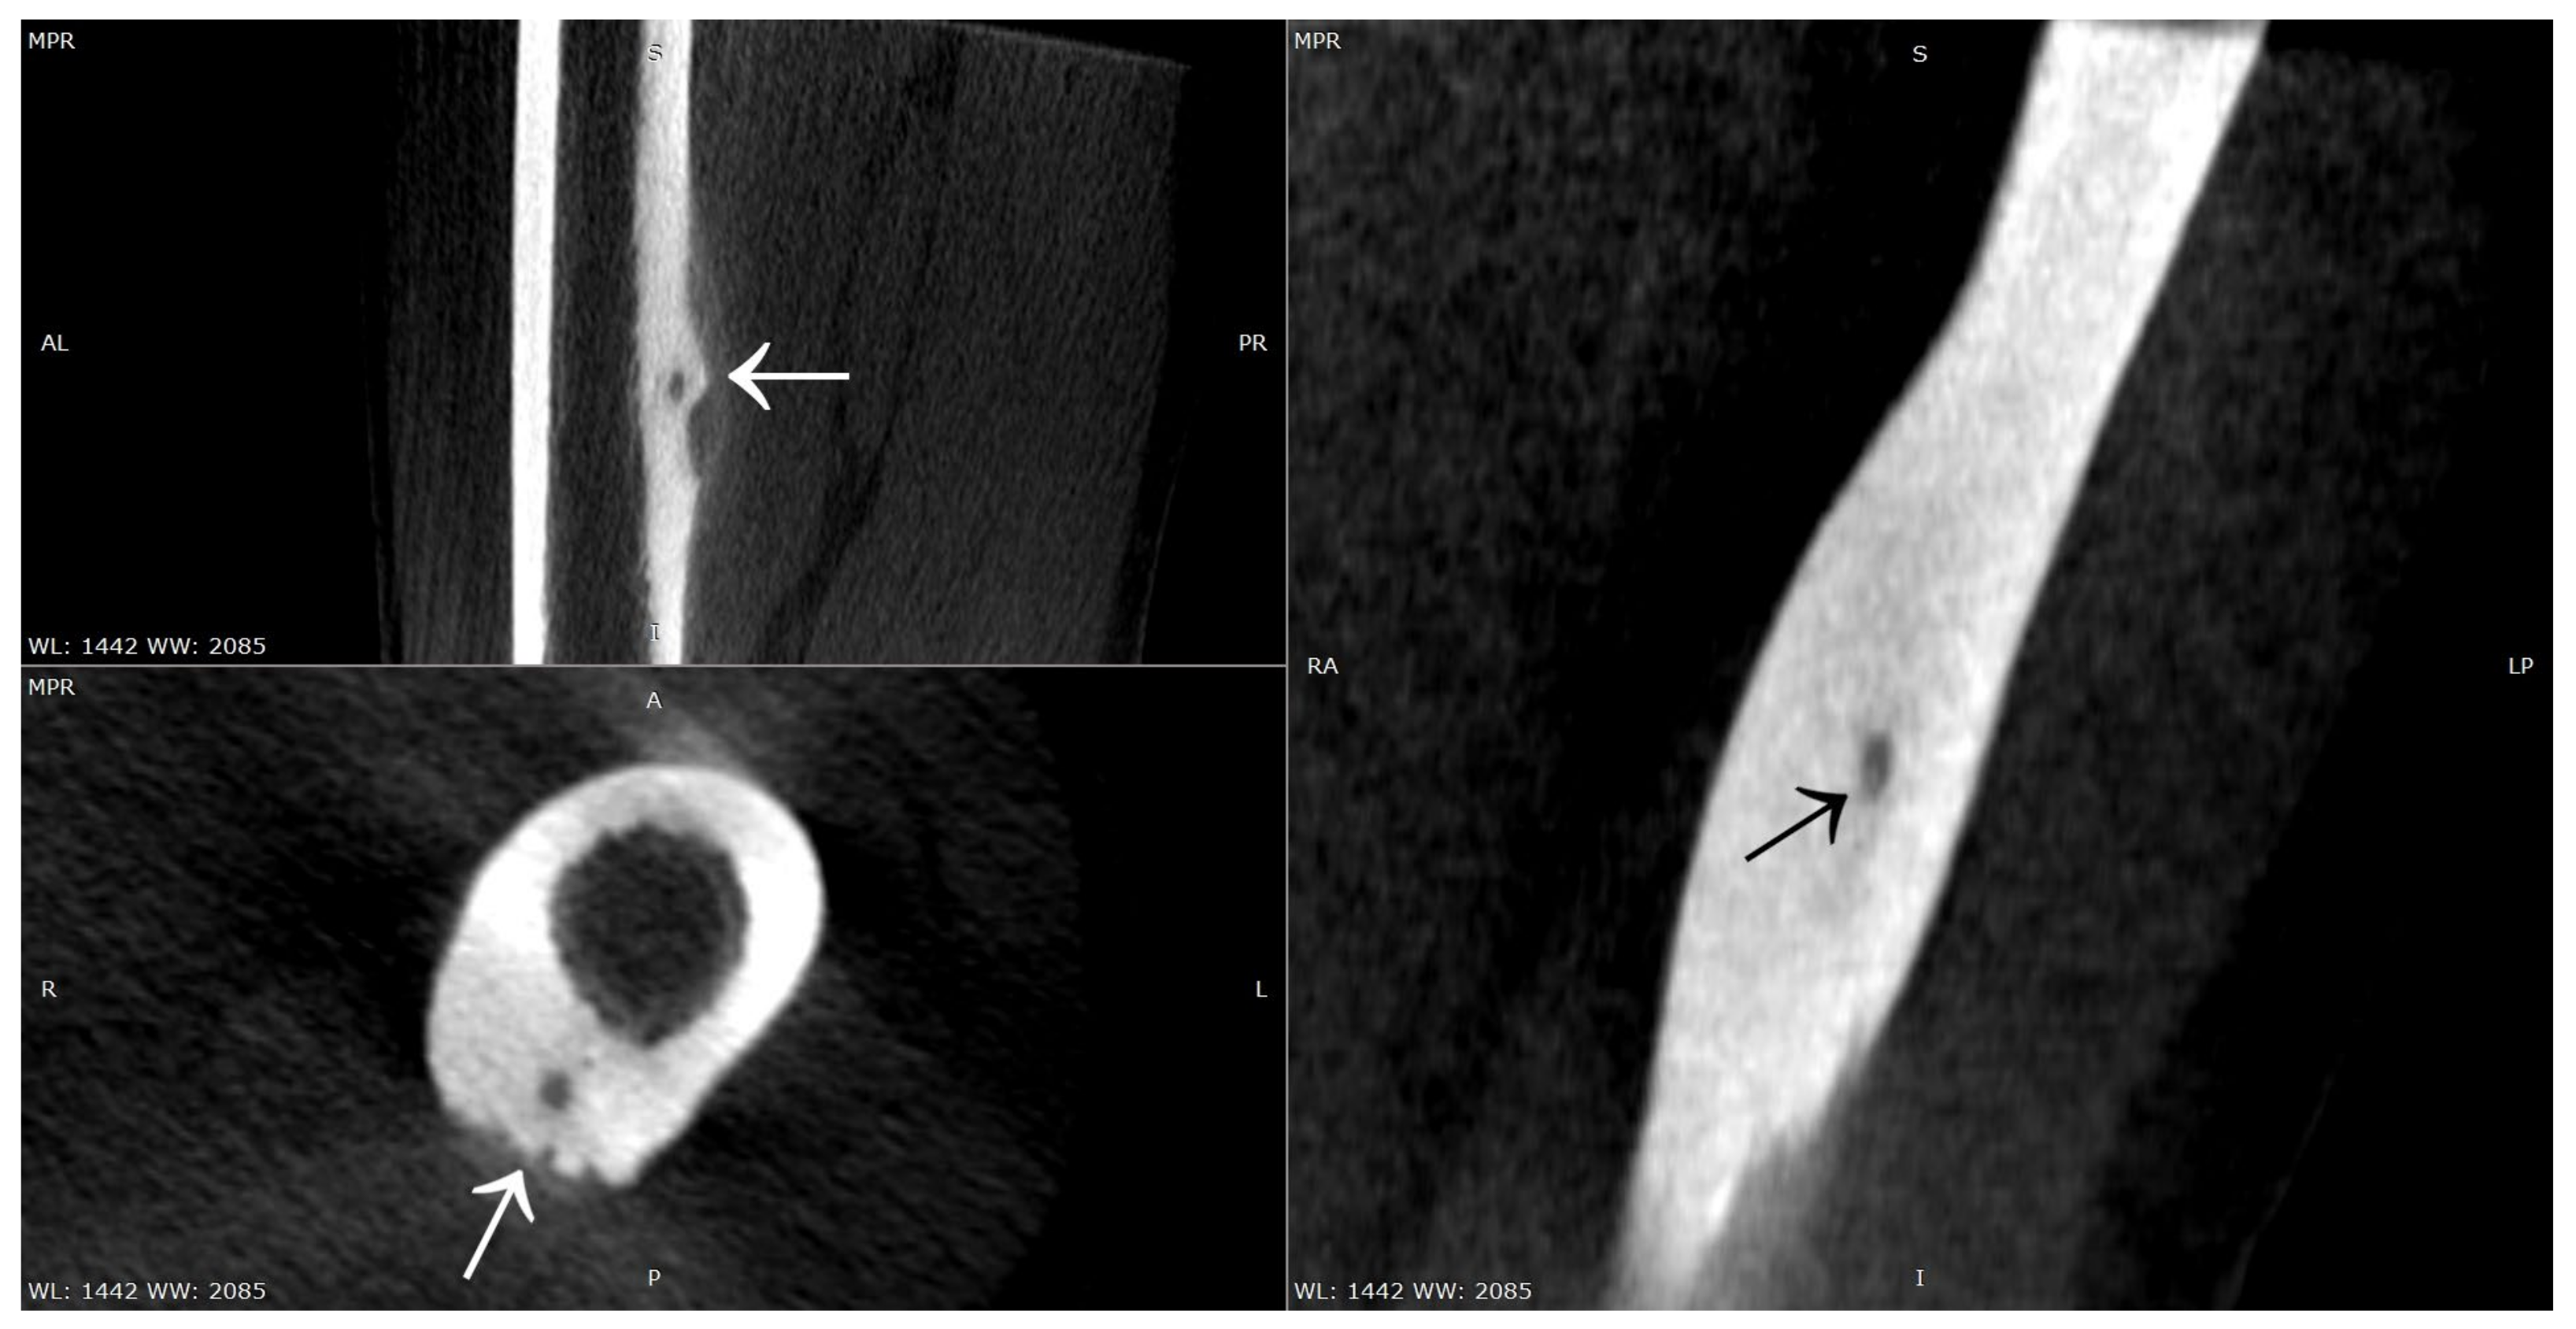

3.4. Case 4: OO Masking as a Fatigue Fracture

3.5. Case 5: OO Masking as Tuberculosis and Juvenile Idiopathic Arthritis